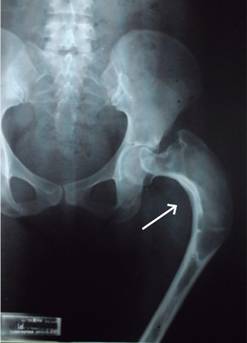

Femenino de 30 años de edad con fractura de cadera izquierda a los 15 años de edad no asociada a evento traumático, el manejo fue conservador y la paciente presentó discrepancia en la longitud de ambas extremidades inferiores por acortamiento del lado afectado. A los 29 años de edad, la paciente se embaraza, durante este tiempo el acortamiento de la extremidad afectada aumentó 5 cm. La radiografía de pelvis mostró deformidad radio-opaca en cabeza femoral izquierda en «cayado de pastor» (Figura 1), datos confirmados por tomografía axial computarizada (Figura 2), por lo que se solicitó valoración por endocrinología manejándola con bifosfonatos y su embarazo concluyó adecuadamente. En el puerperio mediato sufrió caída desde su plano de sustentación, contusión directa en cadera izquierda, dolor, incremento de la deformidad, crepitación ósea y la radiografía simple mostró la deformidad ya mencionada con una fractura subtrocantérica en sitio de displasia, imagen de vidrio despulido, de apariencia quística en cuello femoral, zona trocantérica y subtrocantérica (Figura 3). Ante estos hallazgos se le realizó resección del sitio de lesión y colocación del Sistema Modular de Revisión Femoral ArcosMR (Figura 4). A los 10 meses de la operación la evolución de la paciente era satisfactoria (Figura 5).

Figura 2: Imagen de una tomografía axial computarizada de fémur proximal izquierdo en la que se observa deformidad con intensidades heterogéneas que involucra cuello y cabeza femoral izquierdos.